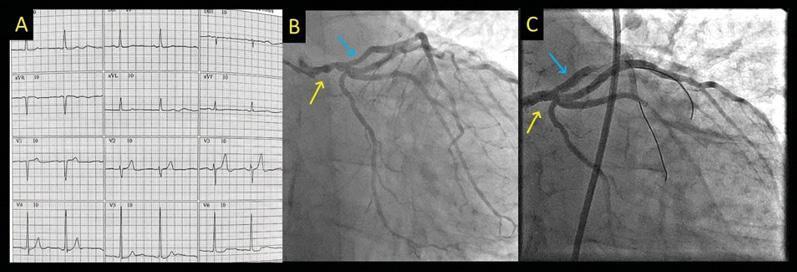

Amiloidose Cardíaca do Tipo Selvagem (ATTRwt) e Regurgitação Aórtica em um Paciente com Leucemia Mielomonocítica Aguda: Uma Combinação Atípica

Embora a amiloidose tenha sido associada a diversos distúrbios malignos, sua associação com a leucemia é bastante incomum.– Além disso, observa-se uma relação entre a AC e a doença cardíaca valvular, especialmente a estenose aórtica (EA). A associação entre a AC do tipo selvagem (AC ATTRwt) e a regurgitação aórtica (RA) em um paciente com leucemia mielomonocítica (LMM) aguda é única e não foi descrita até o momento.